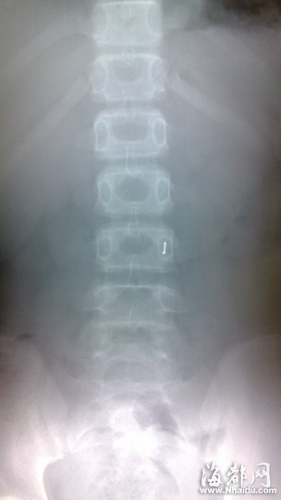

值班医生初步检查三名女生的症状后,安排她们做X光检查。从X光片可看出,她们腹内均存在椭圆状金属异物,且分布在肠子的不同部位。估计是玩具胶囊内含有金属异物,通过食道,滑落到胃里,又下行滑到了肠子。

该值班医生说,在确定金属异物无毒、圆润,不会造成胃穿孔、肠损伤的情况下,让三人吃下保护胃黏膜的药物,开了小剂量的泻药,有助于排泄。